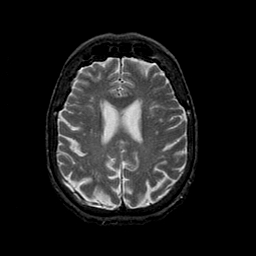

Normal aging, overlay -- Slice #35

[Home][Help][Clinical] Slice 35